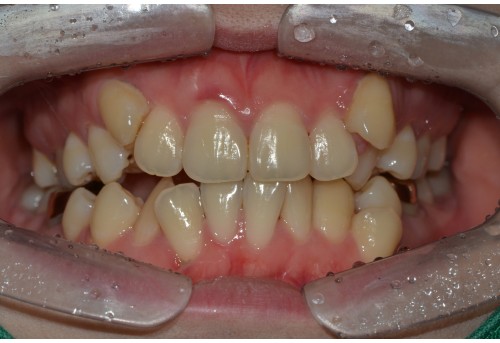

체리 증례집

• 전체

• 치아교정

• 임플란트

• 체리네이트